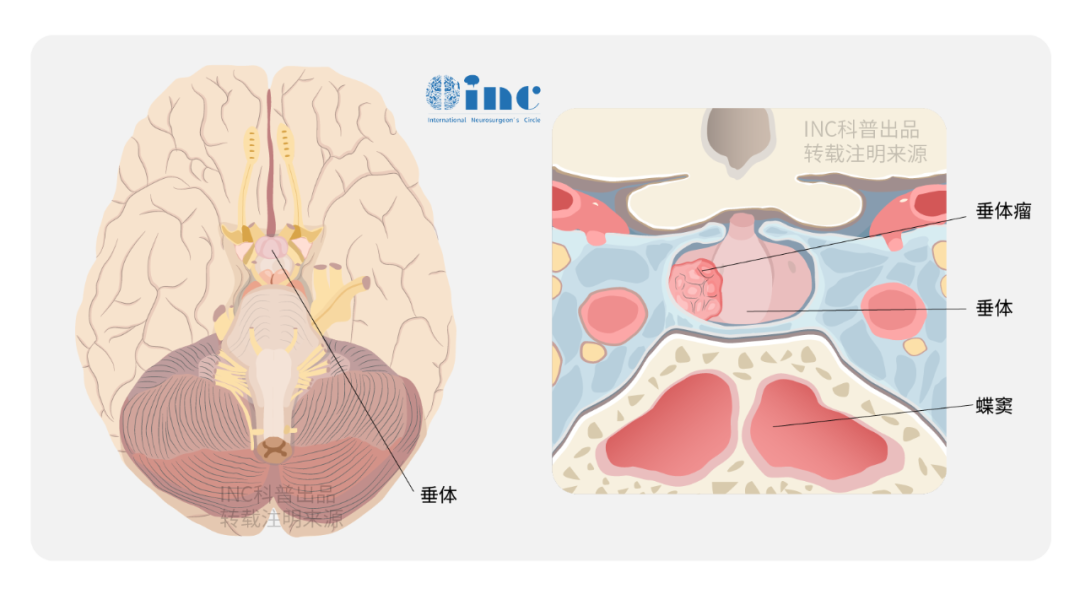

垂体腺瘤(PAs)是良性病变,经鼻蝶窦手术是治疗垂体腺瘤的主要方法,通过积极治疗,部分垂体瘤是不会复发的。然而,如果垂体瘤的病情比较复杂,和周围组织关系紧密,部分垂体腺瘤表现出侵袭性行为,一旦手术达不到全切从而导致复发。垂体功能障碍、侵袭相关风险以及其他并发症对复发性垂体腺瘤患者的生活质量产生了显著影响。

能否完全切除肿瘤取决于多种因素,包括肿瘤的一致性和侵袭性。许多放射影像学特征是手术结果不佳的标志,如多叶的巨大腺瘤、骨质侵袭和海绵窦受累。对功能性和无功能性腺瘤(图1)两者,改良Knosp分级是一个用来预测肿瘤切除率的有用的工具,它描述了腺瘤与颈动脉的关系。